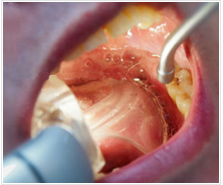

治療中の負担・不快感を軽減する口腔内ライト

当院で採用している口腔内ライトには、奥歯で噛み締めることのできるシリコン製の「バイトブロック」が付属しています。

バイトブロックは奥歯で噛みしめることができるので、口を開けたままの状態でも顎に負担がかかりづらく、

治療時の苦痛を軽減することができます。

口腔内ライトに付属している「舌プロテクション」が、治療中の患者様の舌を保護しますので、治療時の怪我は心配ありません。

また、プロテクションの中であれば舌は自由に動かすことができるので、苦痛は伴いません。

口腔内ライトでは、付属の「バキューム」で、リアルタイムで唾液の吸引が可能です。

患者様ご自身が唾を飲み込む必要はありませんので、不快感を軽減できます。

また、吸引機で無理に吸い込むこともありませんので、痛みもありません。